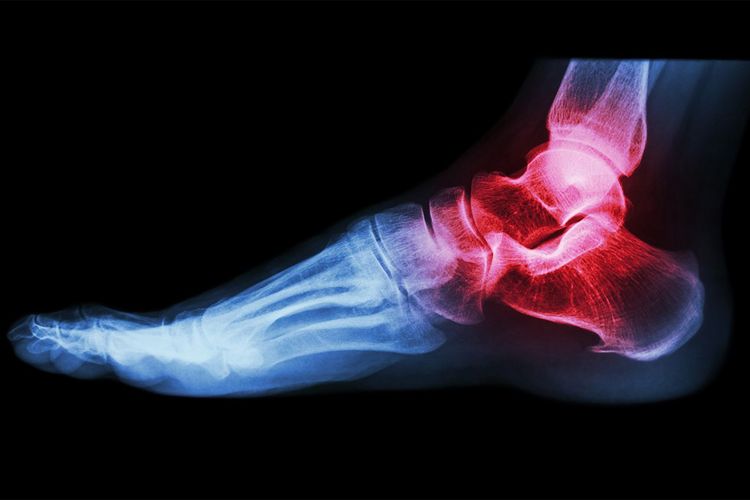

Eine komplexe physiotherapeutische Behandlung ist möglich. Sie erfolgt auf der Station oder in den speziellen Sport- und Behandlungsräumen der Abteilung für Physiotherapie.